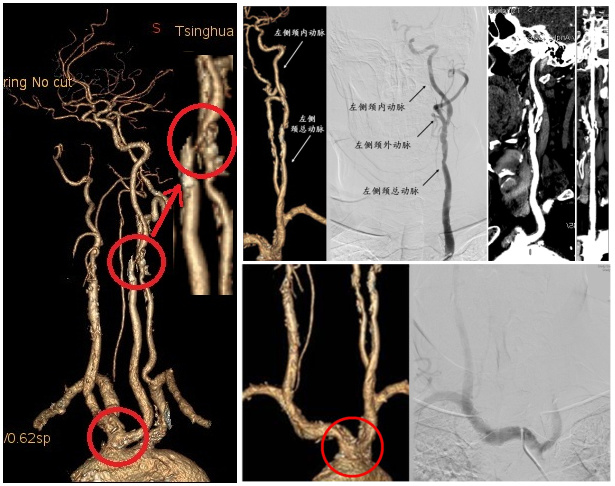

图2 患者CTA与动脉造影对比。A)左侧颈总-颈内动脉长程狭窄。CTA上左侧颈外动脉因数据分析显示缺如,血管造影是血管评价的金标准。B)患者左侧颈内动脉与无名动脉共干,为解剖变异,“牛型弓”带给左侧颈内动脉介入手术操作带来极大困难

北京清华长庚医院针对心血管疾病,成立涵盖心脏内、外科和血管外科的心脏血管中心,联合诊治复杂心血管疾病。由于刘伯伯心脏情况直接危及手术安全,心脏内科张萍主任、王伟民主任、缪国斌主任先行实施冠状动脉造影术,发现刘伯伯心脏的3支主要血管均有问题,左侧冠脉前降支最严重处狭窄80%、回旋支主支远段闭塞100%、右冠主支全程多处狭窄90%,围手术期发生心梗风险极大。紧接着,“换人不换台”,血管外科吴巍巍主任、赵克强主任通过心内科的冠脉造影通路(不增加新伤口)成功完成了全脑造影、双侧颈动脉、椎动脉造影,清晰显示右侧颈内动脉闭塞、左侧颈内动脉重度狭窄,同时弓上分支出现“牛型弓”变异,与放射科CTA检查结果相符合,手术难度极大。麻醉科张欢主任造影全程为患者保驾护航。